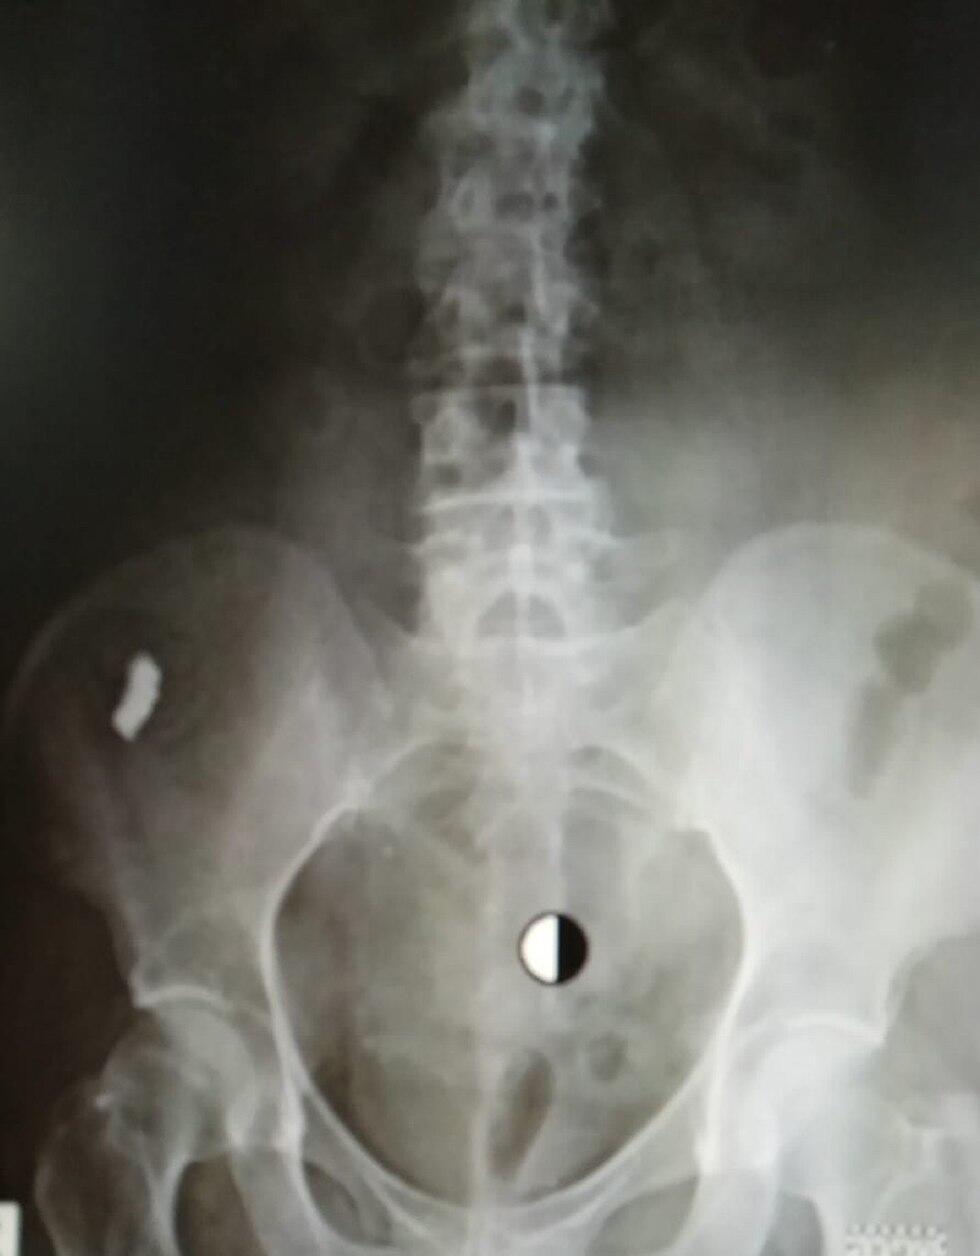

Проглоченный протез на рентгенограмме

Даже много повидавшие в своей практике врачи "Маккаби" были удивлены этим случаем. Рахели срочно сделали еще один рентгеновский снимок.

Габи Лев Толев, заведующий рентгенкабинетом, подтвердил подозрения: протез никуда не вышел, а находится в органах брюшной полости. Он срочно направил Рахели к находящемуся в этом же медпункте доктору Тамезу Мацу, специалисту по заболеваниям внутренних органов.

Доктор Мац тоже отметил, что впервые за 20 лет своей работы встречает подобный случай. По его словам, протез находился в районе толстой кишки.